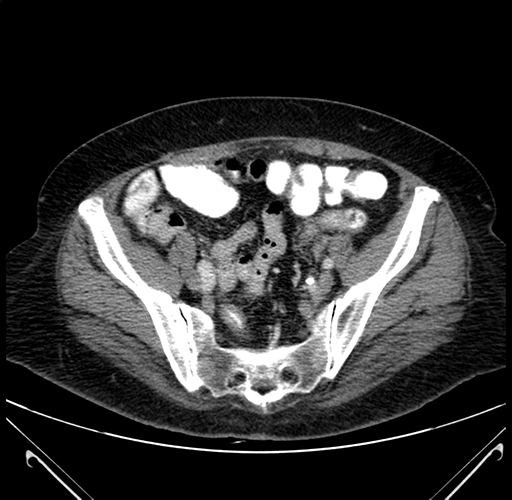

Pre-Chemo: Axial Venous

Axial Venous